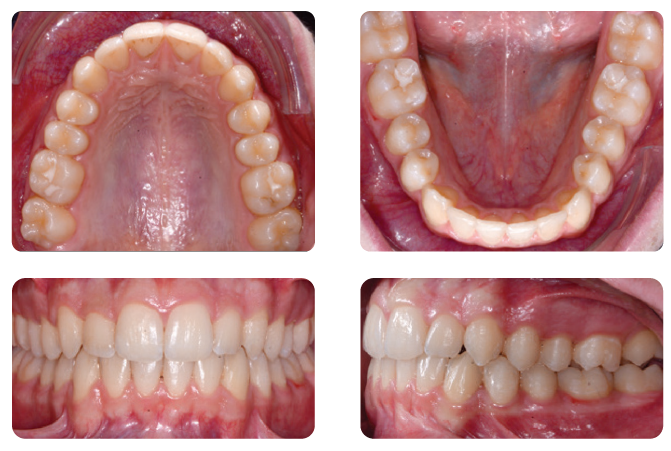

Overlay of initial (white) and post-treatment (green) occlusion in virtual setup viewer. Buccal grip points were planned on the upper right canine and first premolar, upper left canine and first molar, lower right first premolar, and lower left canine and second premolar. In addition, 0.1 mm of interproximal reduction (IPR) was planned at each contact point from the mesial surface of the upper right first molar to the mesial surface of the upper left first molar, and from the mesial surface of the lower left second premolar to the mesial surface of the lower right second premolar. IPR was used to reduce the proclination of both arches and achieve a good anterior relationship with normal overjet and overbite. Aligners were changed every two weeks. After the 12th planned set of aligners, four more were added to the series to refine the result (pictures below).

The clear aligner therapy lasted eight months. Treatment Results Post-treatment records indicated a satisfactory outcome after four months of Carriere Motion Appliance with fulltime Class II elastic wear and eight months of clear aligner therapy.

The patient showed an aesthetic profile and incisor display on smiling, along with a Class I canine and molar relationship. The midlines were centered and the crowding was resolved, but the second molar occlusal contacts were less than optimal, probably because of the presence of a palatal precontact. Post-treatment panoramic radiography evidenced good root parallelism with no sign of crestal bone height reduction or apical root resorption. Cephalometric analysis indicated that the inclination of the lower incisors with respect to the mandibular plane (IMPA) increased slightly, from 96.3° to 9.9°, demonstrating the anchorage control provided by the appliance (check Table 1 in the full article). Superimposition of the pre- and post-treatment cephalometric tracings, according to the method developed by Björk,9,10 highlighted a clockwise rotation of the occlusal plane. The appliance’s control of the vertical height and lower-incisor proclination was clear from the regional superimpositions. Even though the treatment period was short, the superimpositions revealed considerable residual growth in a downward and forward direction, since the initial radiographs were taken six months before treatment began.